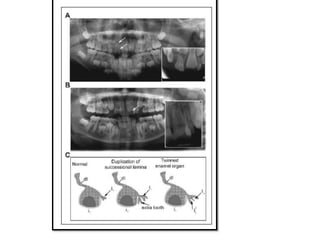

Figure 6. Panoramic radiographs showing duplicated primary and

permanent maxillary central incisors. (A) An 8-y-old male with

duplication of primary maxillary right central incisor (arrow), most

likely formed by gemination of the primary incisor and a supernumerary

tooth. In addition to the primary doubled incisor, a small supernumerary

tooth is visible in the apical region of the primary tooth (arrow).

(B) A 11-y-old male with a permanent maxillary left central incisor

formed by gemination of the permanent incisor and a supernumerary

tooth (arrow). Tooth number remained unchanged. (C) Schematics of

possible mechanisms of double-tooth formation. (middle) Duplication of

successional lamina leads to formation of 2 joined teeth. (right) Splitting

of the developing tooth bud leads to the formation of geminated tooth.

dl, dental lamina; i1, first primary incisor; I1, first permanent incisor; I2

1,

supernumerary permanent incisor.

Figure 6. Panoramicradiographs showing duplicated primary and permanent maxillary central incisors. (A) An 8-y-old male with duplication of primary maxillary right central incisor (arrow), most likely formed by gemination of the primary incisor and a supernumerary tooth. In addition to the primary doubled incisor, a small supernumerary tooth is visible in the apical region of the primary tooth (arrow). (B) A 11-y-old male with a permanent maxillary left central incisor formed by gemination of the permanent incisor and a supernumerary tooth (arrow). Tooth number remained unchanged. (C) Schematics of possible mechanisms of double-tooth formation. (middle) Duplication of successional lamina leads to formation of 2 joined teeth. (right) Splitting of the developing tooth bud leads to the formation of geminated tooth. dl, dental lamina; i1, first primary incisor; I1, first permanent incisor; I2 1, supernumerary permanent incisor.